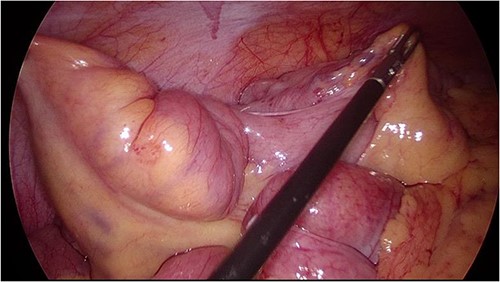

She then underwent an elective diagnostic laparoscopy which showed a cicatrizing small bowel mass in distal ileum ~15 cm from TI (Figs 3 and 4), with a normal appendix and no other abnormalities. There were no stigmata of endometriosis, and no free fluid or blood in the pelvis/abdomen. A wedge resection of the mass with a side-to-side small bowel anastomosis and planned removal of the appendix (due to pre-operative concerns of further adhesions in the area) was performed.

Intraoperative image at laparoscopy showing dilated distal small bowel loop and tethered TI (unable to straighten out bowel).